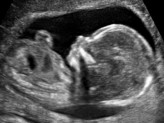

ഗര്ഭസ്ഥശിശു മരിച്ചതറിയാതെ രണ്ടാഴ്ച ഉദരത്തില്പേറി ആദിവാസി യുവതി

ഗര്ഭസ്ഥശിശു മരിച്ചിട്ടും അതറിയാതെ ആദിവാസി യുവതി രണ്ടാഴ്ച കുഞ്ഞിനെ ഉദരത്തില്പേറി നടന്നു. കുഞ്ഞു മരിച്ചിട്ടും ചികിത്സയൊന്നു നല്കാതെ യുവതിയെ വീട്ടില് പറഞ്ഞുവിടുകയായിരുന്നു. വേങ്ങൂര് പൊങ്ങന്ചുവട് ആദ...

അവരുടെ ആഗ്രഹം സഫലമായി; ഏറെ നാളത്തെ കാത്തിരിപ്പിനൊടുവില് കിട്ടിയത് നാലു കണ്മണികളെ...

എറെ നാളത്തെ കാത്തിരിപ്പിനൊടുവില് അജിതയ്ക്ക് പിറന്നത് നാലു കണ്മണികള്. ചേര്ത്തല പട്ടണക്കാട് ശാന്തിനികേതനില് ശശികുമാറിന്റെ ഭാര്യ അജിത (47)ക്കാണ് ആദ്യപ്രസവത്തില് നാലു കുട്ടികള് ജനിച്ചത്. ഇതില് മൂന...